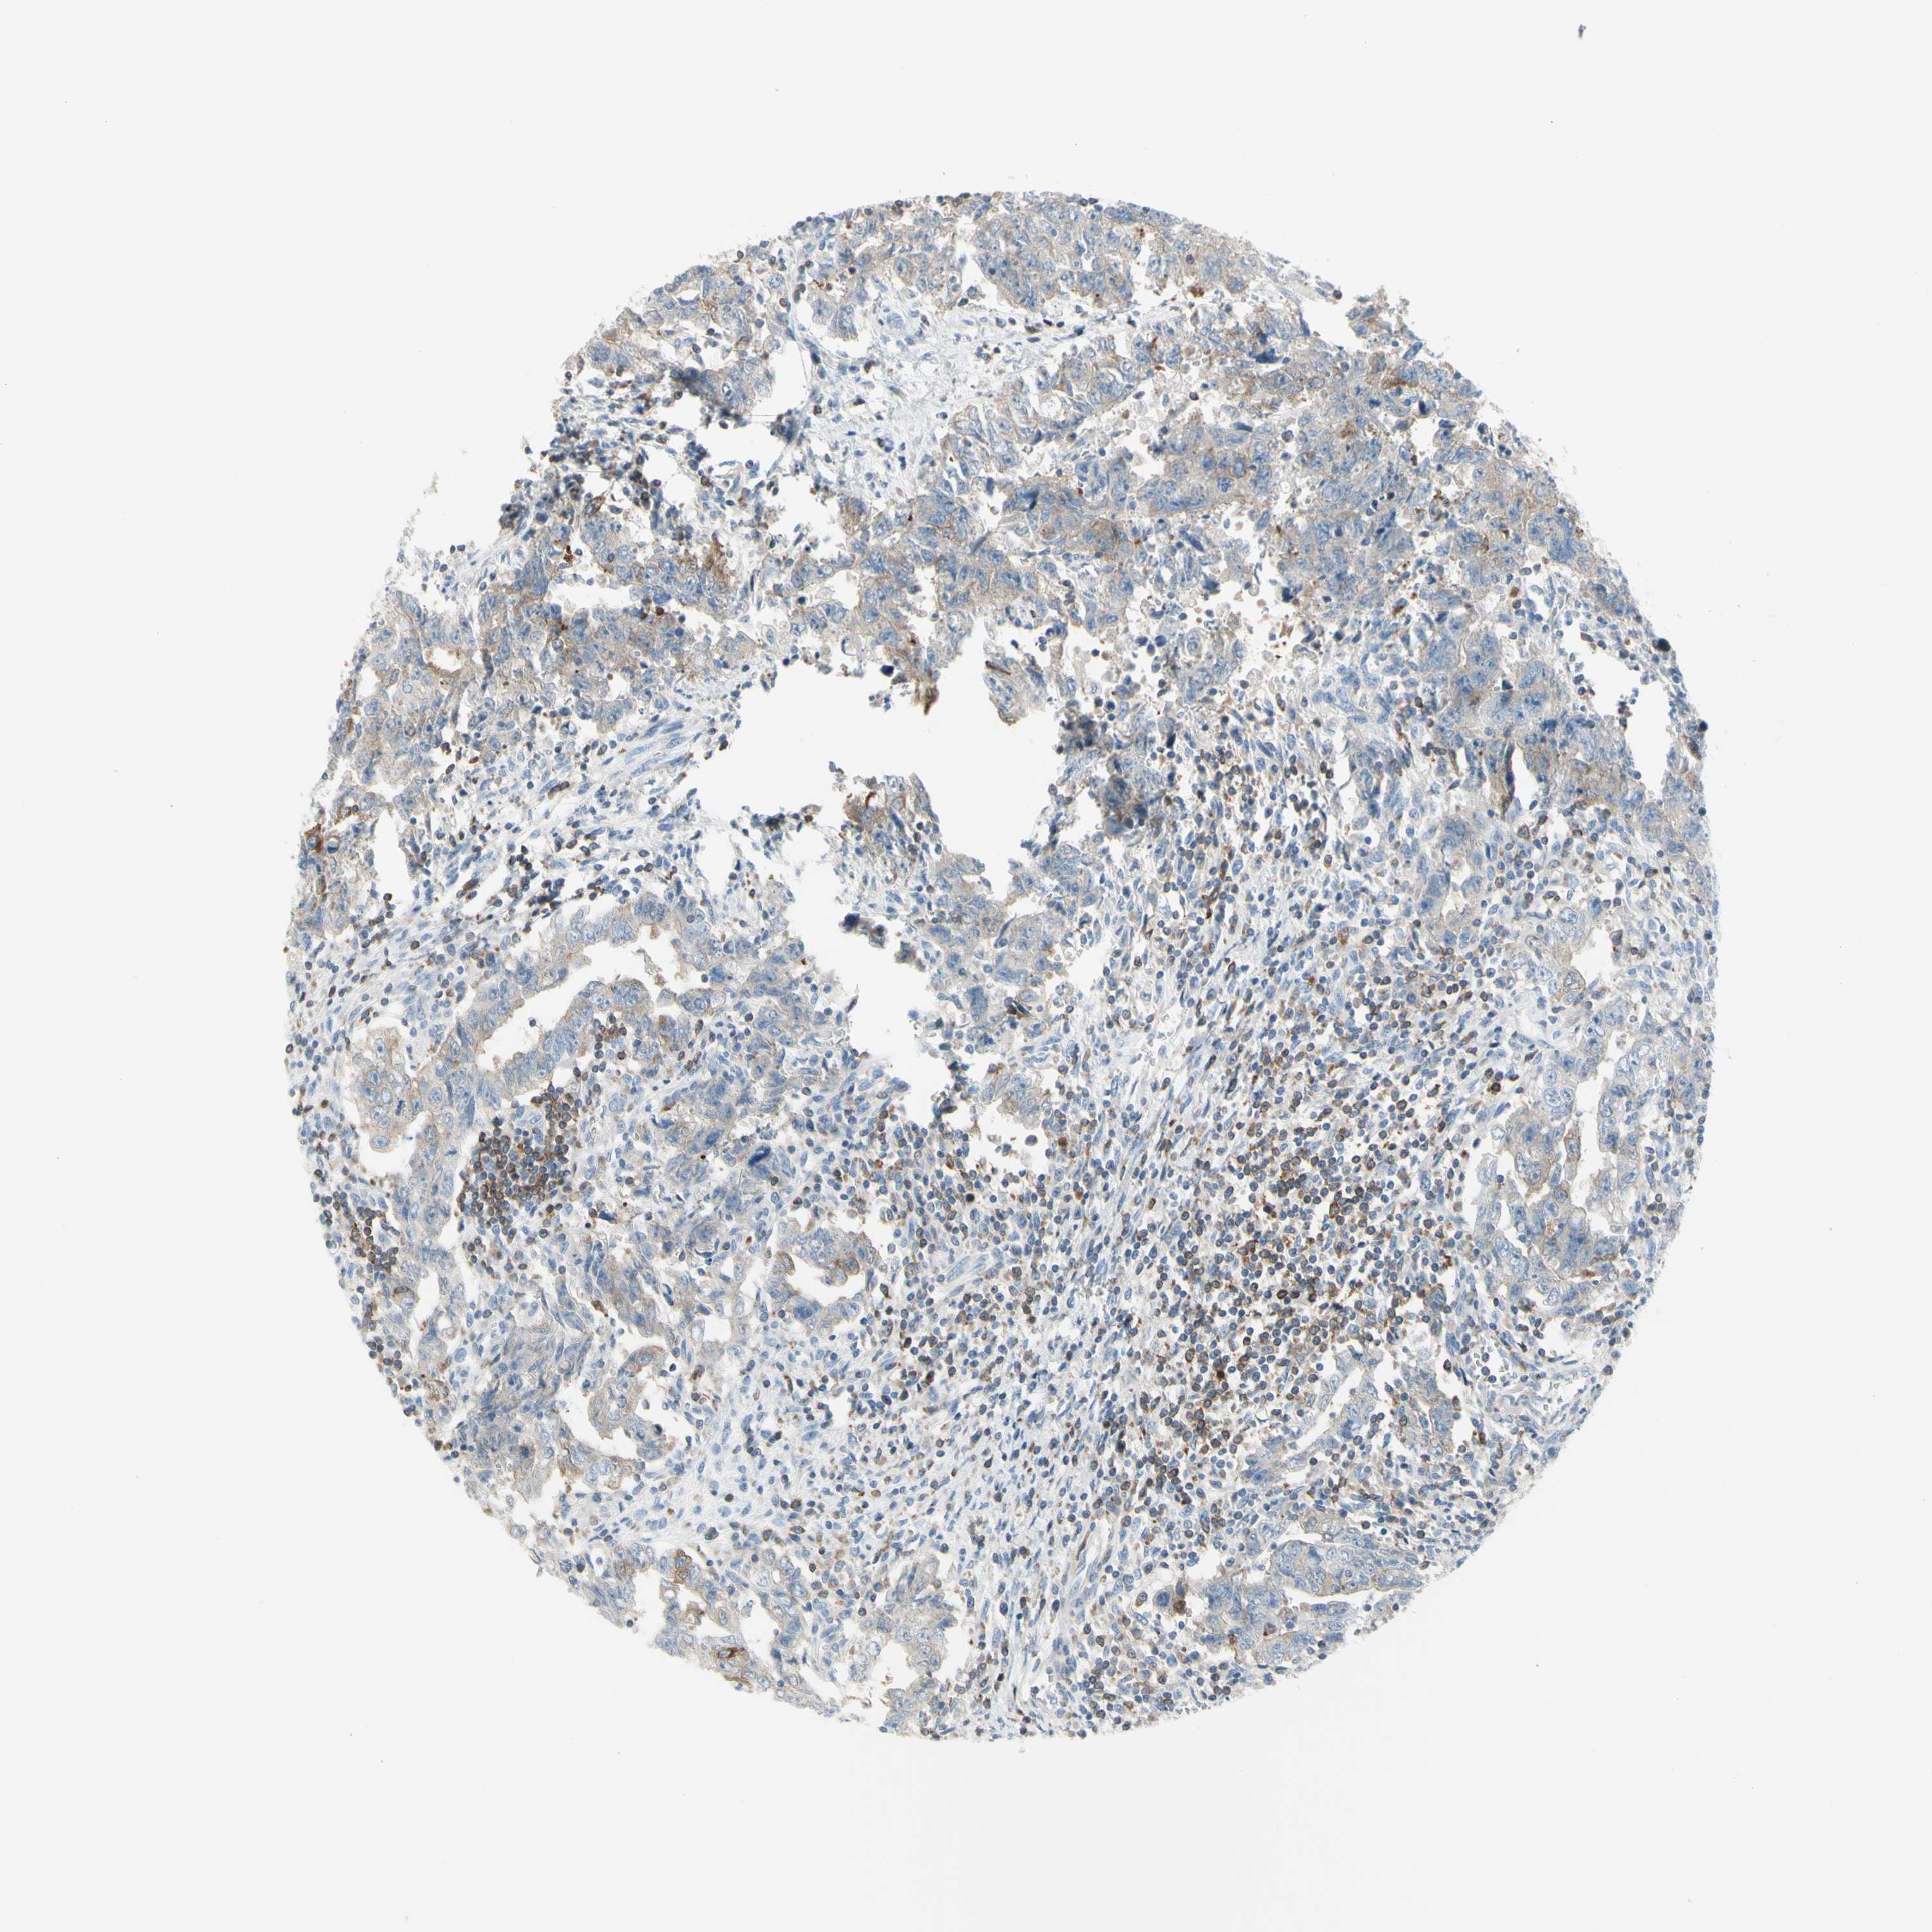

TESTIS CANCER - Protein expressioni

A mouse-over function shows sample information and annotation data. Click on an image to view it in a full screen mode. Samples can be filtered based on level of antibody staining by selecting one or several of the following categories: high, medium, low and not detected. The assay and annotation is described here.

Note that samples used for immunohistochemistry by the Human Protein Atlas do not correspond to samples in the TCGA dataset.

Antibody stainingi

Antibody staining in the annotated cell types in the current human tissue is reported as not detected, low, medium, or high, based on conventional immunohistochemistry profiling in selected tissues. This score is based on the combination of the staining intensity and fraction of stained cells.

Each image is clickable and will lead to virtual microscopy that enables deeper exploration of all samples and also displays staining intensity scores, fraction scores and subcellular localization as well as patient and tissue information for each sample.

HPA004179

HPA007235

HPA008855

CAB000036

CAB001986

CAB080102

CAB080103

Carcinoma, Embryonal, NOS

Seminoma, NOS

Teratoma, malignant, NOS

Urothelial carcinoma, High grade